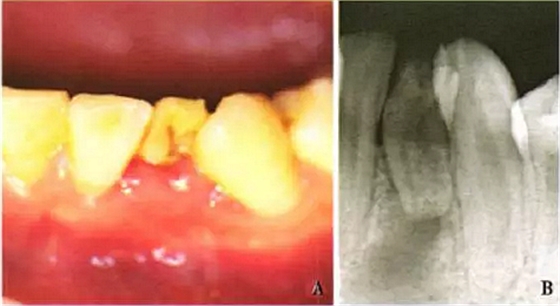

患者,男,17歲,因下頜左前牙區(qū)自發(fā)痛咬合痛4d前來就診??谕鈾z查未見明顯異常,口內(nèi)檢查見32(FDI牙位表示法)牙冠形態(tài)異常,舌側(cè)窩較對(duì)側(cè)同名牙深,唇側(cè)有一深凹陷(圖1A);32叩診陽性,牙髓活力測(cè)顯示無牙髓活力,I度松動(dòng);唇側(cè)牙齦略紅腫,探診出血,未探及牙周袋;鄰牙未見明顯異常。根尖片示32牙冠與牙根形態(tài)異常,且牙根短小,其根尖周圍見x線透射區(qū)(圖1B)。

A:口內(nèi)唇側(cè)像示下頜左側(cè)切牙牙冠異常;B:32牙內(nèi)陷,根尖周圍較大范圍X透射區(qū)

圖1 32牙內(nèi)陷